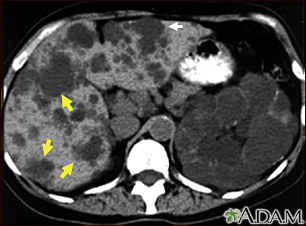

Esta TC abdominal muestra quistes en el hígado y los riñones (enfermedad poliquística). El hígado es el órgano grande situado en la parte izquierda de la pantalla. Las manchas oscuras sobre el hígado son los quistes.